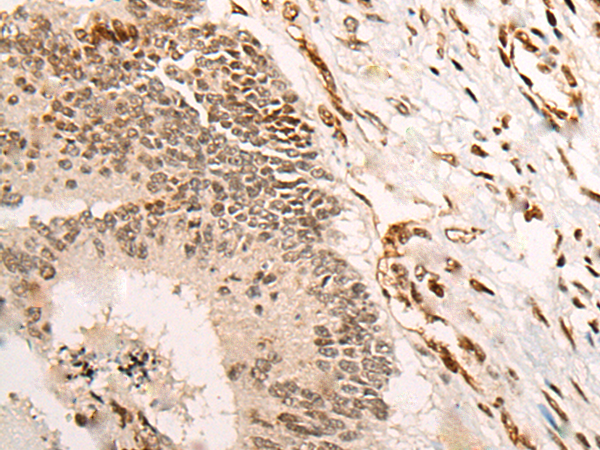

分类: 科研抗体货号: P05984别名: ZNF631应用: IHC反应种属: Human